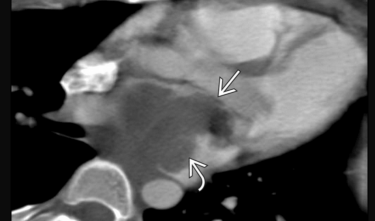

Metastases de mélanome VD et OD

Metastases de mélanome VD et OD

Metastase myocardique melanome progressif

Metastase myocardique melanome progressif